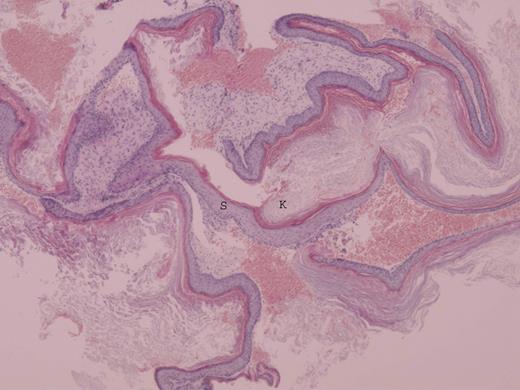

At surgery, transmeatal exicision of the EAC osteoma revealed an underlying cholesteatoma that has caused bony erosion of the inferior canal wall (Fig. 2) and formed a fistulous connection to the overlying neck skin (Fig. 3). The post-aural sinus and fistula were excised through a post-auricular incision. A cortical mastoidectomy was performed to explore the mastoid cavity, which was found to be disease free. The temporalis fascia was harvested and used to reconstruct the inferior canal wall defect. Histopathologic examination of the excised tissues confirmed the synchronous dual pathology involving the EAC (Figs 4 and 5).

Photomicrograph of cholesteatoma showing stratified squamous epithelium (S) and overlying lamellar sheets of keratin (K) (H&E ×10).

Histopathologically, this is represented as a focal hyperplastic squamous epithelium of the EAC with accumulation of chronic inflammatory cells in the adjacent stromal tissue. Invasive growth of the EAC cholesteatoma into the deeper mesenchymal tissue results in accumulation of necrobiotic keratin debris in the newly formed central cavity. This is pathognomonic for the diagnosis of EAC cholesteatoma [6].